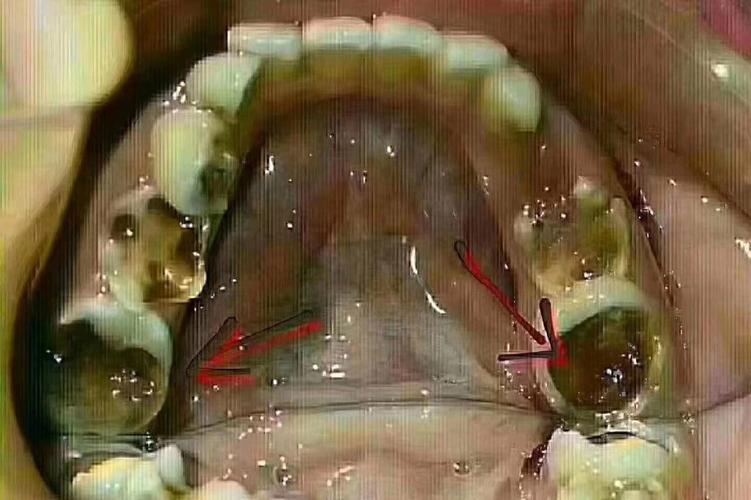

六龄齿,即第一恒磨牙,通常在6岁左右萌出,是口腔中最早萌出的恒牙,承担着重要的咀嚼功能,同时对维持颌骨发育、建立正常咬合关系具有不可替代的作用,由于萌出早、窝沟深,六龄齿也容易发生龋坏,若未及时治疗,严重时可能需要拔除,许多家长和患者会担心:六龄齿缺失后还能进行正畸治疗吗?六龄齿缺失并非正畸的绝对禁忌症,但治疗方案需根据患者的年龄、口腔具体情况、缺失原因及正畸目标综合制定,需通过全面评估后才能确定可行性和具体策略。

六龄齿位于牙弓后部,是咬合的关键支撑点,缺失后可能引发一系列口腔问题:

- 邻牙移位:缺牙间隙两侧的第二前磨牙和第二磨牙会向缺隙倾斜、移位,导致牙弓长度缩短,排列紊乱;